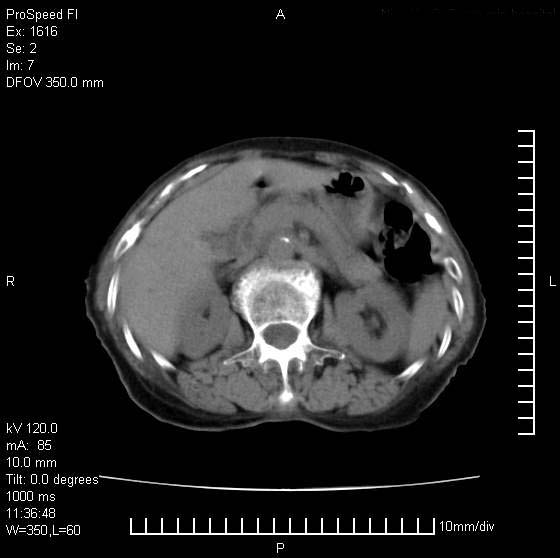

患者无明显临床症状,肝左叶发现一个圆形密度不均的低密度灶,边界较清楚,大小37x45mm,ct值35-70,患者犹豫做增强,如有增强片,我再发上,现先请各位老师会诊.

左肝外叶可见较大圆形低密度影,病灶可见较光整清晰边界,病灶内可见多量条状稍高密度影,右肝前叶亦可见圆形结节状低密度影,边界清晰,密度均匀,考虑1肝多发囊肿,左肝囊肿内出血2肝包虫病3左巨块型肝癌出血合并右肝转移或合并右肝囊肿

条带壮高密度影好象胃窦粘膜?考虑:1-慢性肝脓肿.2-胃窦溶积效应

病灶内高密度影,从ct值上看是血的密度还是某种纤维组织呢?似乎有内缘有包膜,肝脏各叶比例略失调,脾脏有点大.

hcc(巨块型)伴出血,突破肝包膜,肝胃韧带内,腹主动脉旁淋巴结转移;肝硬化

肝左叶不均匀占位,内有斑片状高密度出血灶,内侧缘似有假包膜,腹主动脉周围及肝门区结构紊乱,似有增大淋巴结,考虑:肝左叶hcc并淋巴结转移。建议增强扫描除外其他。